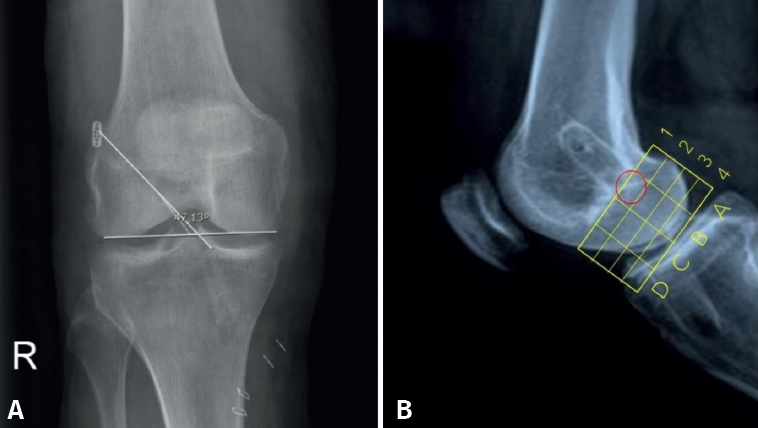

El posicionamiento del TF se evaluó mediante dos proyecciones radiológicas realizadas un mes después de la intervención: una proyección AP y otra de perfil (P) a 30° de flexión. El aparato de rayos Siemens Ysio® S y Siemens Axion Aritos® MX/VX se utiliza a una distancia de 1,5 metros. Las mediciones se realizaron con el programa informático Raim Alma. La proyección coronal permite estudiar la orientación del TF. Se mide el ángulo formado entre la superficie articular bicondilar y el TF. Revisando estudios previos incluidos en la bibliografía, un ángulo menor de 30° o mayor de 55° se asocia con reconstrucciones insuficientes del LCA y mayor riesgo de rotura(10). La vista sagital indica el posicionamiento de la entrada del TF en el área intercondílea femoral externa. Se utiliza el método del “cuadrante femoral”(11) según el cual se toma como referencia la línea de Blumensaat (intercondílea posterior), que sirve de guía para elaborar el eje de coordenadas que se muestra en la Figura 4A.

Paralelamente a la línea de Blumensaat, se traza otra línea a nivel de la superficie articular y este espacio se divide en 4 zonas horizontales del mismo grosor mediante otras 3 líneas paralelas. Los 4 espacios obtenidos constituyen el eje de ordenadas y se numeran de proximal a distal con los números 1, 2, 3 y 4.

Perpendicularmente a la línea de Blumensaat y con la superficie articular anterior y posterior como límite, la superficie se divide en 4 espacios de igual longitud. Estos espacios constituyen el eje de abscisas, que se identifican de posterior a anterior con las letras A, B, C y D. El correcto posicionamiento del TF para la inserción femoral del LCA corresponde al área delimitada según este eje de coordenadas del método del cuadrante femoral con los valores B1 y B2 que se muestran en la Figura 4B. El principal resultado radiológico fue la posición del TF, que se llevó a cabo mediante dos proyecciones radiológicas un mes después de la intervención: una proyección AP y una P a 30° de flexión. La proyección AP se utilizó para medir el ángulo formado entre la superficie articular bicondilar.